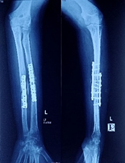

Case-IV

39 years, female;

Comminuted fracture distal humerus (Figure 14-17).

Figure 14 Post-operative x-ray after Ilizarov operation.

Figure 15 Picture with Ilizarov frame.

Figure 16 X-ray after union.

Figure 17 Picture after union.